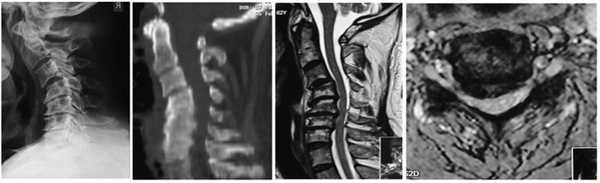

На рентгенограммах и снимках мультиспиральной компьютерной томографии (МСКТ) шейного отдела позвоночника выявлены кифотическая деформация, нестабильность позвоночника, при проведении МРТ отмечены признаки передней компрессии, деформации спинного мозга (рис. 2). Рис. 2. Рентгенограмма и снимок МСКТ позвоночника (сагиттальная проекция), МРТ позвоночника (сагиттальная и аксиальная проекции) — тип В деформации позвоночника.